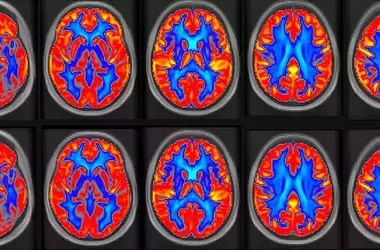

A new study sheds light on how neurodiverse children manage sensory overload, suggesting an adaptive brain mechanism. These findings reveal that children highly sensitive to everyday stimuli may unconsciously adjust their brain networks to mitigate overwhelming sensory input. This research, published in the Journal of Neurodevelopmental Disorders, identifies a distinct neural signature that could redefine our understanding of sensory processing challenges.

Researchers investigated the distinct brain activity patterns in neurodiverse children who experience heightened sensory reactions. Their findings indicate that these children often exhibit reduced connectivity in outward-facing brain networks responsible for processing external sensory data, alongside elevated activity in inward-focused networks governing attention and cognitive control. This suggests an adaptive strategy where the brain minimizes external sensory input while enhancing internal regulatory mechanisms to maintain composure in overwhelming environments.

The study, conducted by a multidisciplinary team from the University of California, San Francisco, utilized magnetic resonance imaging (MRI) on 83 neurodiverse children aged 8-12. Participants were divided into groups based on their sensory over-responsivity, excluding those with confirmed autism to ensure sample consistency. The imaging revealed a 'double dissociation': children with sensory over-responsivity showed decreased connectivity in exogenous (outward-facing) networks and increased connectivity in endogenous (inward-facing) networks. Conversely, neurodiverse children without sensory issues displayed the opposite pattern. This pattern, particularly strong in resilient children with sensory over-responsivity, suggests an unconscious coping mechanism where the brain downregulates external sensory processing while upregulating internal cognitive control to manage intense stimuli and maintain emotional balance. The researchers also noted reduced structural integrity in white matter pathways associated with visual and motor signals in sensory-sensitive children.

This research identified that the distinct brain pattern of low sensory connectivity and high regulatory connectivity is particularly prominent in resilient children with sensory over-responsivity. This indicates that this neural signature might be an adaptive mechanism, enabling these children to cope with sensory overload by unconsciously suppressing external sensory input and boosting internal cognitive control. Machine learning algorithms successfully classified children with and without sensory over-responsivity with nearly 90% accuracy using functional MRI and white matter data, suggesting a robust biological basis for the condition. However, the study's limitations, including a relatively small sample size and the exclusion of children with autism, highlight the need for future longitudinal studies to track brain network development and explore the impact of interventions like occupational therapy. Understanding whether these brain patterns precede sensory issues or develop in response to them will be crucial for effective early intervention and treatment.